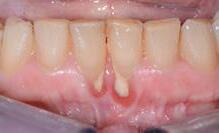

Figure 7.1 Récessions gingivales multiples.

Figure 7.2 : Récessions gingivales sur les 2 incisives centrales mandibulaires. L’absence de gencive attachée sur les faces vestibulaires rend le brossage pénible et délicat. La gencive est inflammatoire. Une greffe est nécessaire pour recréer un bandeau de gencive kératinisée.